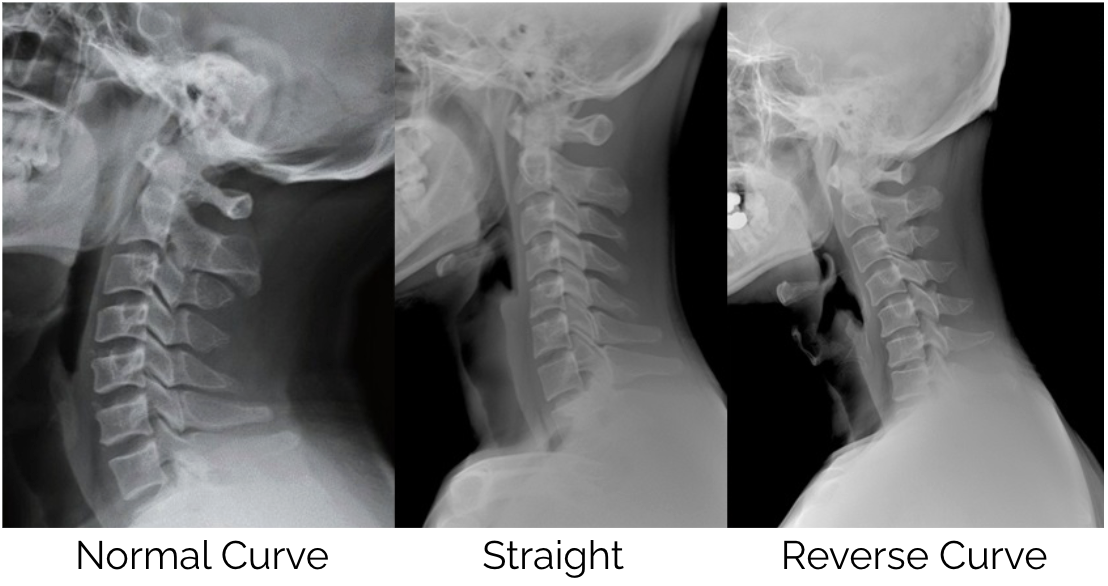

The consequences of sustained forward head posture extend well beyond local neck pain and muscle tension. Dr Hansraj’s research (1) also noted that spending several hours per day in poor posture can begin to alter the natural curvature of the cervical spine over time — a change that is far more difficult to address once it becomes established.

As Chiropractors, we have seen a shift over the past 10-20 years with more people losing the natural curve of the cervical spine and an increase in reversed curves which is a result of excessive time looking at handheld devices.